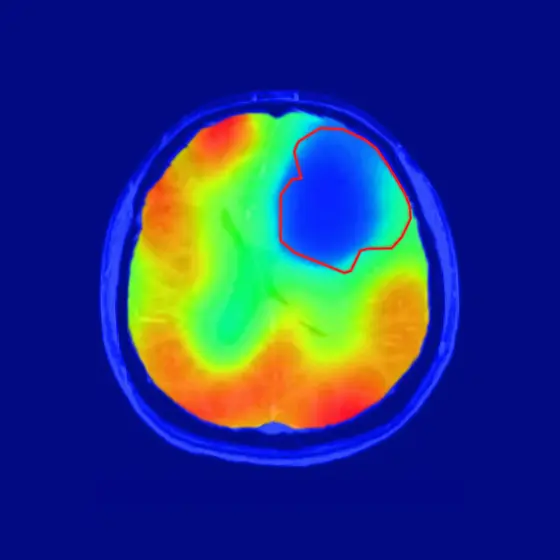

Die rote Linie markiert das Tumorareal; der farbige Kontrast zeigt den Sauerstoff-Stoffwechsel an. Wie vom Warburg-Theorem vorhergesagt, ist der Sauerstoff-Umsatz im Tumor reduziert (blau).

Die neue Technik der DKFZ-Forscher kommt ganz ohne Radioaktivität aus und zeigt zudem sehr spezifisch den Sauerstoff-abhängigen Stoffwechsel des Gewebes. Die Wissenschaftler verwenden eine stabile, nicht radioaktive Variante des Sauerstoffs, 17O2, die in geringen Mengen auch in der Atemluft vorkommt. Die Probanden atmen diesen besonderen Sauerstoff in angereicherter Form ein. Überall, wo in den Körpergeweben Sauerstoff verstoffwechselt wird, geht 17O2 eine Verbindung mit Wasserstoff ein. Dadurch wird es im Magnetfeld des MRT nachweisbar. Gewebe, das viel Sauerstoff umsetzt, erscheint daher im Bild hell.

Die DKFZ-Wissenschaftler um Paech und seinen Kollegen Sebastian Niesporek haben das Prinzip zunächst bei drei gesunden Probanden durchgespielt. Wie erwartet lassen deren Gehirne in der Bildgebung einen hohen Sauerstoffumsatz erkennen. Dann untersuchten die Forscher zehn Probanden, bei denen ein Gehirntumor diagnostiziert worden war, mit der neuen Sauerstoff-MRT. „Das Ergebnis war wirklich eindrücklich: Die Tumoren erschienen im Bild als dunkle Flecken, weil hier kein Stoffwechsel mit Sauerstoff stattfand“, schildert Paech. „Uns hat überrascht, dass dies sowohl bei höhergradigen aggressiven Tumoren als auch bei weniger aggressiven niedriggradigen Tumoren der Fall war.“ Bislang war nicht klar, ob der Warburg-Effekt auch bei niedriggradigen Hirntumoren gleichermaßen eine Rolle spielt.